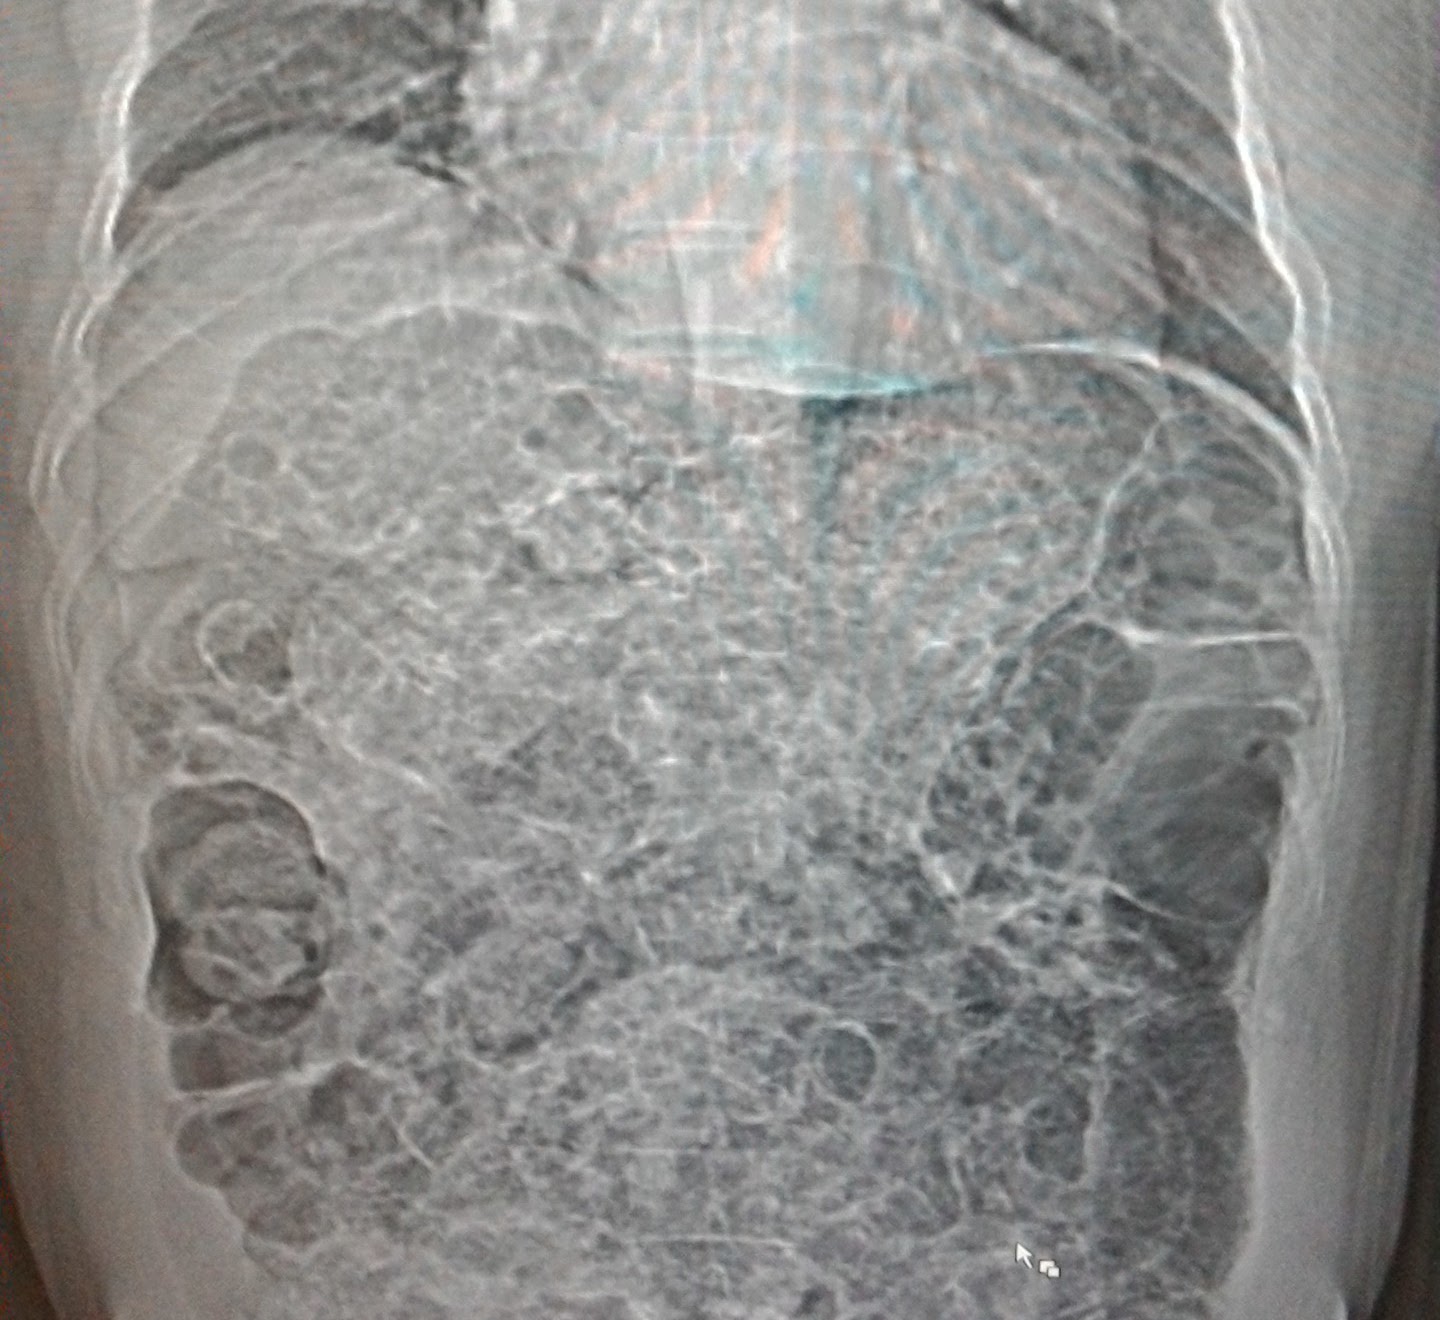

Air bubbles everywhere in the abdomen What Causes Air Bubbles In The Stomach Instead, it builds up in. Intestinal gas is air that collects in a person’s digestive system. Most belching is caused by swallowing excess air. Gastric emphysema has to do with the abnormal presence of air inside the stomach wall. Learn about symptoms, causes, diagnosis, treatment, and outlook for this condition. Belching is the way most swallowed air leaves the stomach.. What Causes Air Bubbles In The Stomach.

Chest radiograph shows gastric bubbles occupying the left thoracic What Causes Air Bubbles In The Stomach Most stomach gas is released when you burp. Gas normally enters your digestive tract when you swallow air and when bacteria in your large intestine break down undigested carbohydrates. Belching is the way most swallowed air leaves the stomach. Gastric emphysema has to do with the abnormal presence of air inside the stomach wall. Instead, it builds up in. Gas. What Causes Air Bubbles In The Stomach.

A) chest Xray showing stomach dilation, prominent gastric air bubble What Causes Air Bubbles In The Stomach Gas may also arise as a byproduct of digesting certain. Too much upper intestinal gas can come from swallowing more than a usual amount of air. Most stomach gas is released when you burp. Most belching is caused by swallowing excess air. Instead, it builds up in. It also can come from overeating, smoking,. This is usually caused by eating. What Causes Air Bubbles In The Stomach.